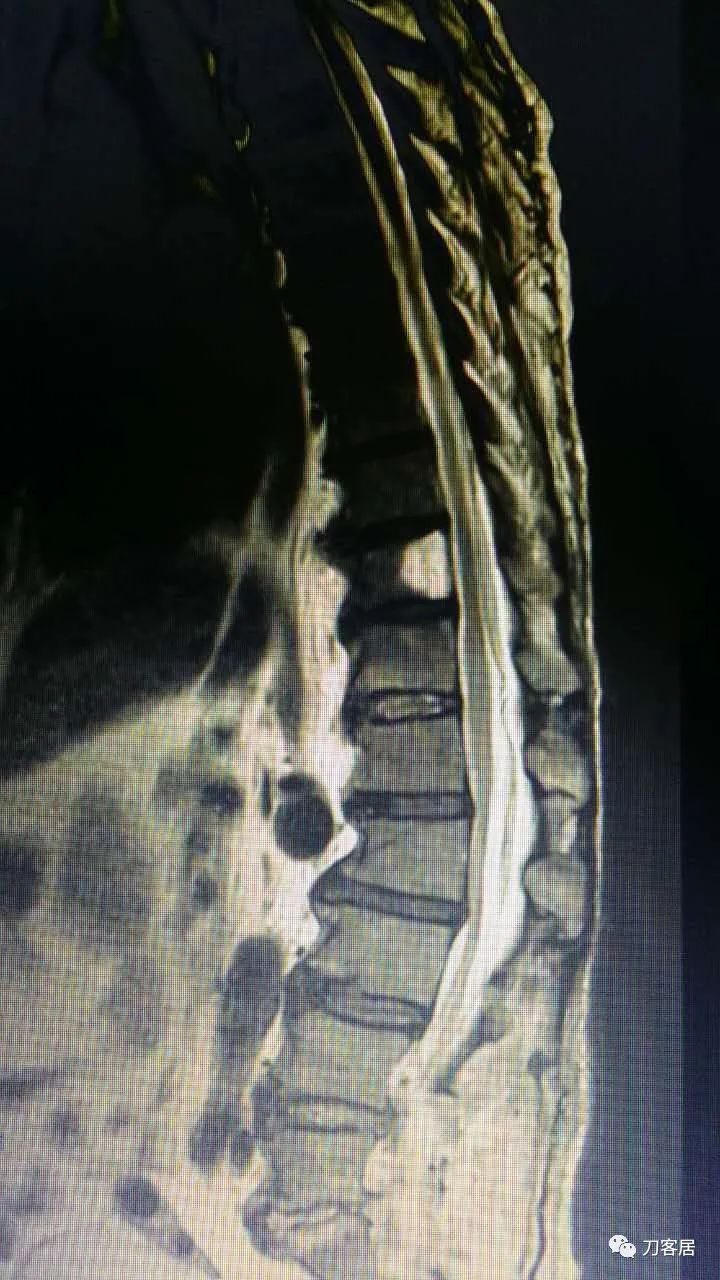

加注图14. 胸9-10椎管内后方高信号占位病变,考虑血肿形成。

加注图15. 胸9-10椎管内后方高信号占位病变,考虑血肿形成。

加注图16. 胸9-10椎管内后方高信号占位病变,考虑血肿形成。

加注图17. 胸9-10椎管内后方高信号占位病变,考虑血肿形成。

加注图10: 腰1-2椎管内后方可见梭形占位信号改变。

加注图11. 腰1-2椎管内后方可见梭形占位信号改变。